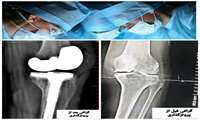

انجام عمل جراحی تعویض مفصل در بیمارستان جوین

رئیس بیمارستان قمربنی هاشم(ع)گفت:عمل جراحی پروتزگذاری (توتال آرتوروپلاستی)دیگری در بیمارستان جوین با موفقیت رقم خورد.